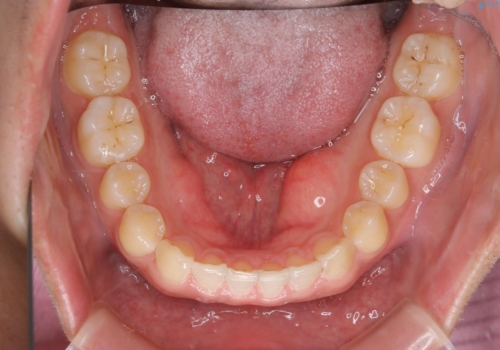

- 上のすきっ歯が気になるとご相談にいらした方です。上下顎ともにスペースがあったため、インビザラインFULLにて見た目と噛み合わせの改善も同時に行いました。

元々は上前歯のみの部分矯正をご希望されていましたが、下の歯もスペースがあり、噛み合わせ的にも上のみの部分治療は難しいことをお話ししました。前歯のみの部分矯正を行った場合、前歯の隙間だけが閉じて奥歯が噛めなくなってしまう場合もあります。インビザラインFULLにて治療することで、噛み合わせと見た目を同時に改善させることができ、大変喜んでいただけました。